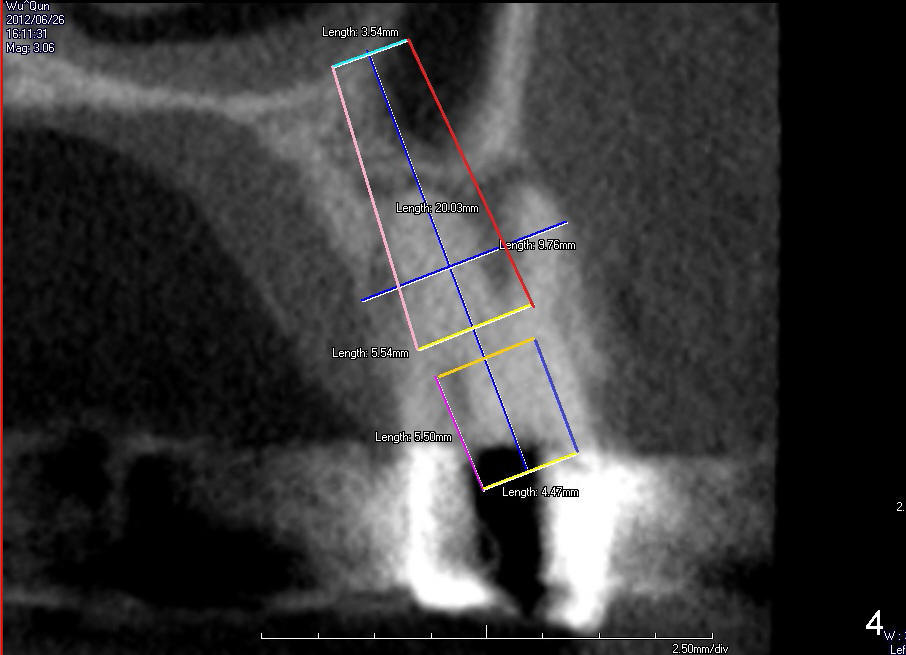

The tooth #13 has broken down to residual root now. CBCT sagittal (Fig.1,3) and coronal (Fig.2,4) sections show designs of T (4.5x17 mm Fig.1,2) and D2 (Fig.3,4) implants. Which is better? It appears that sinus lift with bone graft is expected.

In fact, D2 implant is placed.